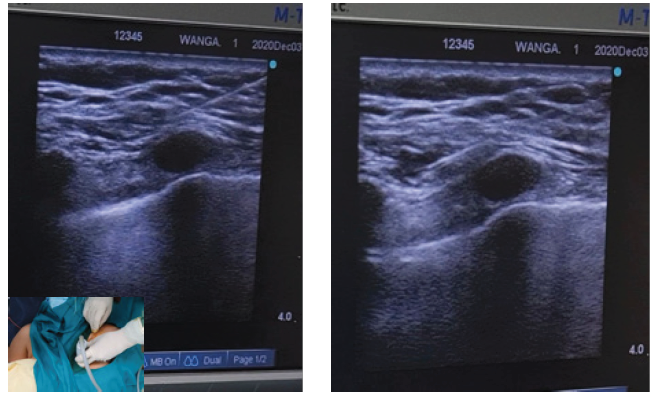

For the first injection, a 22-gauge needle was inserted, placed between the pectoralis minor and major muscle, injecting 10 ml of 0.25% bupivacaine (Fig. 2A). Hydrosection was observed between both muscle, blocking the medial and lateral pectoral nerves. The second injection was made between the pectoralis minor and serratus anterior muscle, injecting 20 ml of 0.25% bupivacaine with intention of blocking long thoracic, thoracic intercostal T2-T6 and thoracodorsal nerves (Fig. 2B). This Pecs II block procedure took about 15 minutes and onset time of analgesia was 15 minutes after completion, confirmed by pinprick test.

Figure 2. The 22-gauge needle was placed between pectoralis major and minor muscle for the first injection with 10 ml of 0.25% bupivacaine (A), then advanced to fascia between pectoralis minor and serratus anterior muscle, injecting 20 ml of 0.25% bupivacaine (B)